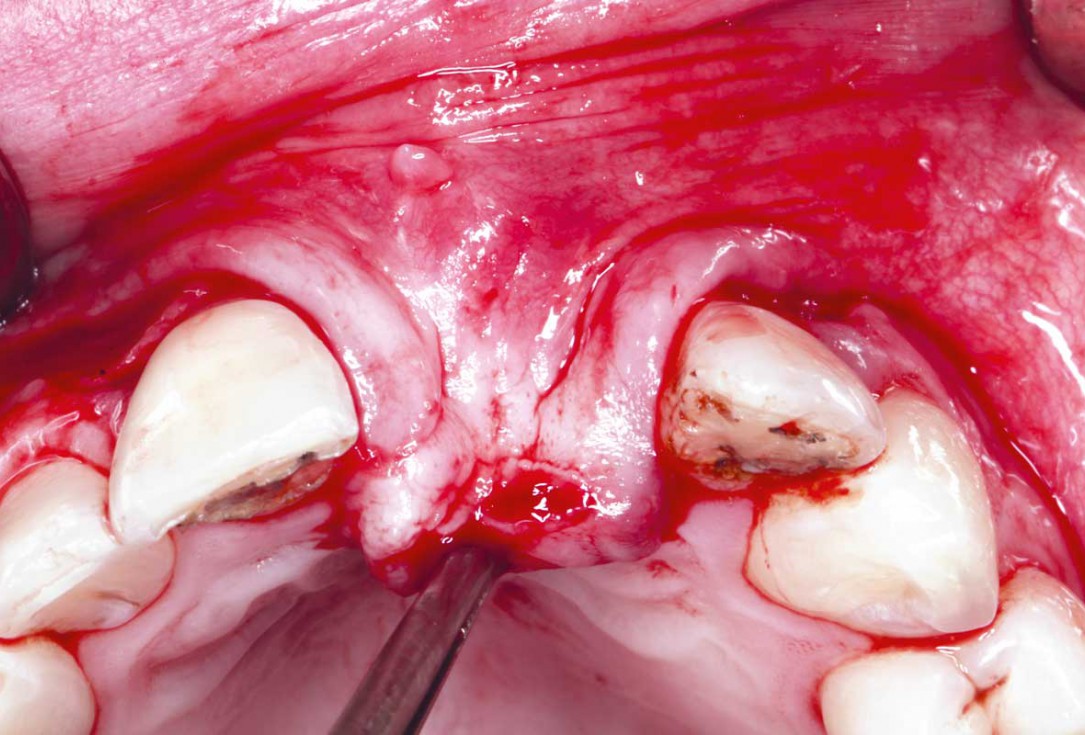

22/35 - Osteotomy prepared revealing a well integrated and nourished bone blockBlock grafting in the aesthetic zone with maxgraft®, Jason® membrane and cerabone® - Dres. H. Maghaireh and V. Ivancheva

23/35 - Implant is placed 3 mm away from the cementoenamel junction. Good primary stability was achieved with a torque of 35 Nom at placement and good block integrationBlock grafting in the aesthetic zone with maxgraft®, Jason® membrane and cerabone® - Dres. H. Maghaireh and V. Ivancheva